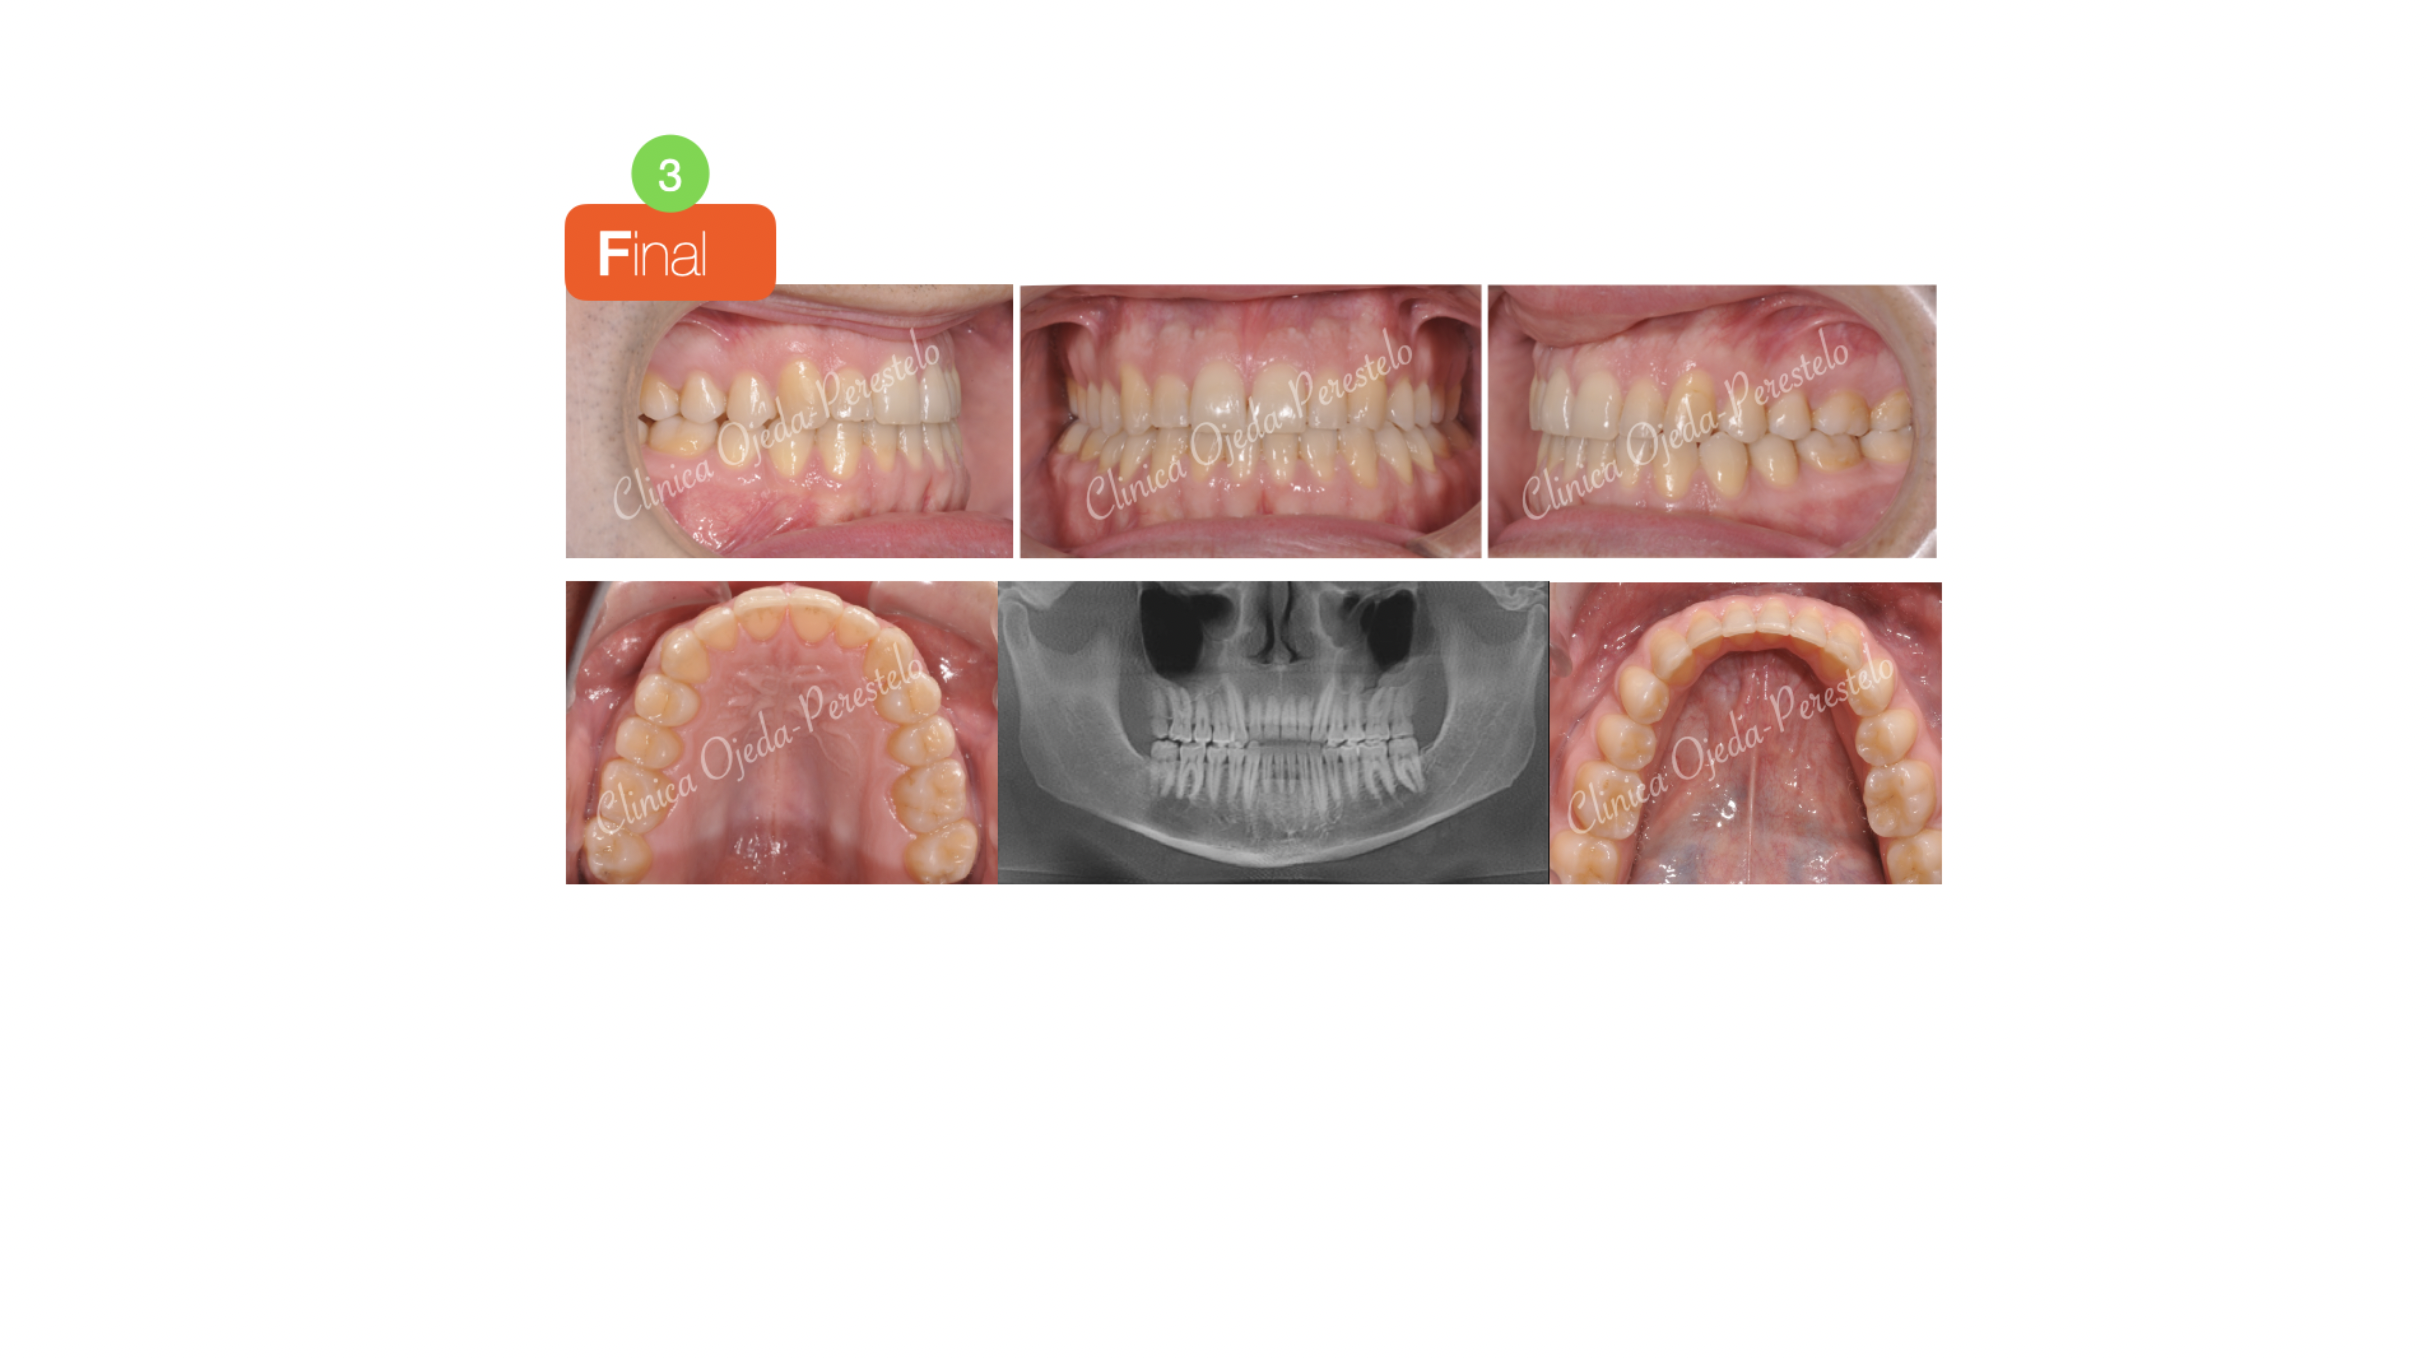

Clase III ósea tratada con Exo de cordales y Microtornillos

Paciente tratado con brackets de autoligado activo (Sistema In-Ovation) donde hemos alineado, nivelado y expandido ambas arcadas. Además hemos realizado las extracciones de los cordales inferiores y colocado Microtornillos para retruir la arcada mandibular al haber descartado el paciente la posibilidad de realizarse una cirugía ortognática.

Quisieramos destacar cómo hoy en día es posible distalizar y retruir con Microtornillos toda la arcada dentaria dotandole a estos casos de un adecuado resalte y sobremordida. Todo ello con una óptima cinemática mandibular.